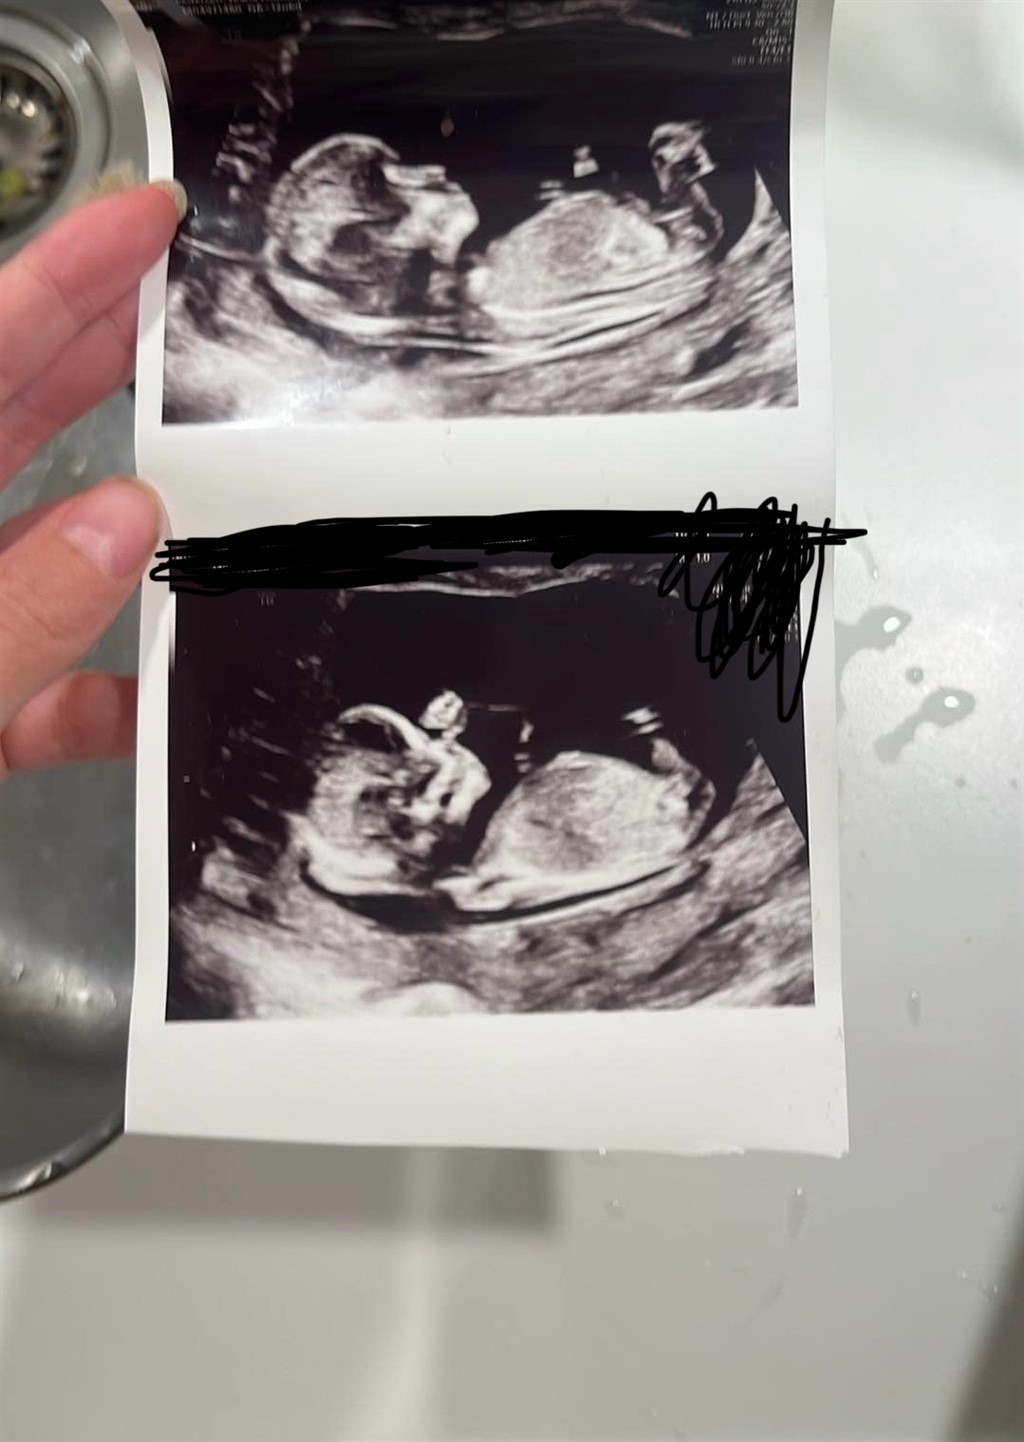

Jeg søger andres vurdering af kønnet ud fra nub teorien.

Jeg var til scanning 12+6 og fik de her billeder med mig